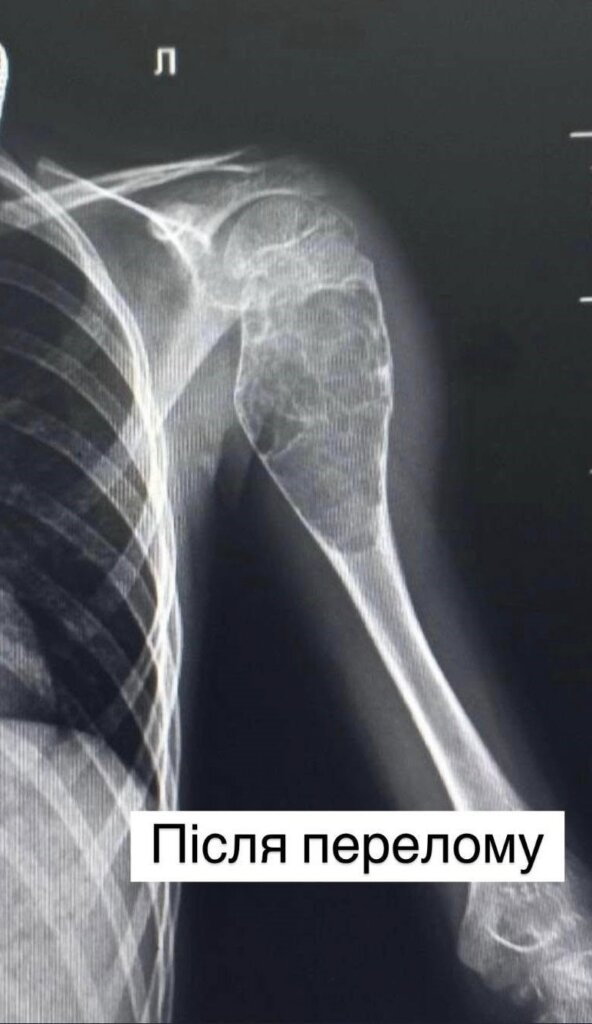

Все почалося в 2022 році, коли хлопчик впав під час збирання грибів. У лікарні наклали гіпс. Та незабаром ситуація повторилася – загалом у Івана було 8 переломів у тому самому місці – лівій плечовій кістці.

Однак наполегливість та цілеспрямованість матері врятувала Івана. Вона після пошуків у інтернеті та за порадами знайомих звернулася до фахівців львівського Охматдиту. Проведені рентген-знімки в динаміці показали: часті переломи спричинені пухлиноподібним утворенням у кістці.

Після усіх обстежень ортопеди-травматологи лікарні провели складну операцію: виконали внутрішню кісткову резекцію – видалили пухлину розміром 9 см на 4 см та замістили дефект кістковими аллотрансплантатами. А також провели металоостеосинтез кістки двома гнучкими титановими стержнями, щоб уникнути повторних переломів. У післяопераційному періоді рука дитини була іммобілізована тільки косинковою пов’язкою, без використання важкої та громіздкої гіпсової пов’язки.

“Кістка була настільки розм’якшена, що буквально провалювалася під невеликим натиском. Ще трохи – і вона могла б зруйнуватися повністю”, – розповідає ортопед-травматолог Олег Токай.

Матеріал пухлини передали на гістологічне дослідження для детального аналізу та встановлення остаточного діагнозу. Гістологія підтвердила, що це аневризмальна кіста.